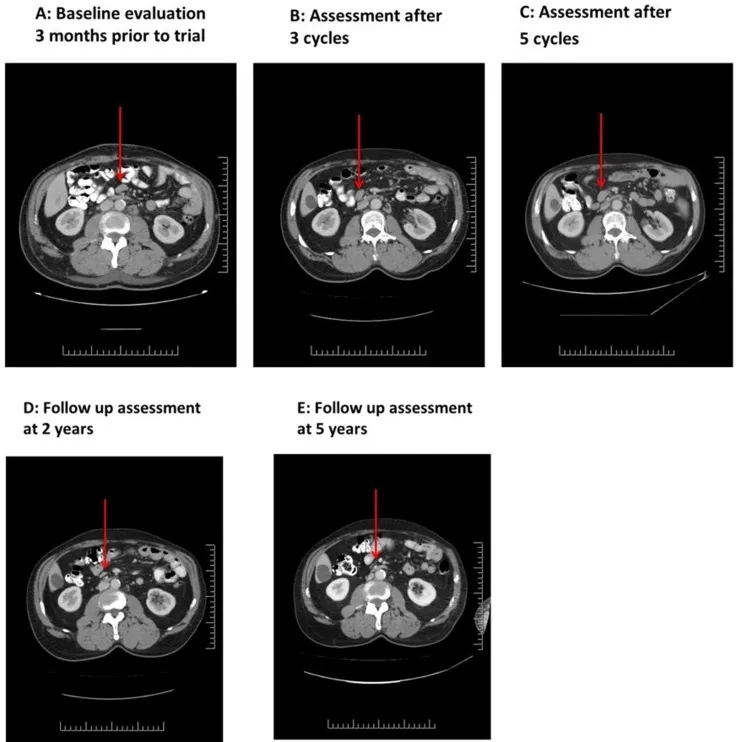

结果显示:疗效呈现明显阶段性特征:治疗前CT显示,双侧腋窝最大淋巴结长轴2.5cm,肠系膜及主动脉旁可见1cm淋巴结(详见下图A)。治疗第1周期第23天中期评估为病情稳定,最大腋窝淋巴结略有缩小;3个周期结束后,影像学显示部分淋巴结缩小(详见下图B);5个周期结束时,影像学提示淋巴结略有肿大(详见下图C),但后续24个月内所有病灶均实现缓解(详见下图D、E)。

▼此例患者(03号)在接受NK-92细胞治疗前后的连续CT扫描对比

治疗期间,患者因皮肤带状疱疹感染引发急性播散性脱髓鞘性脑脊髓炎,经类固醇治疗并在6个月内缓慢减量后,神经系统功能完全恢复。停止所有抗癌治疗后,患者持续维持临床与影像学缓解状态。截至研究随访(距入组已10年),患者无相关症状,且未检测到肿瘤活性。